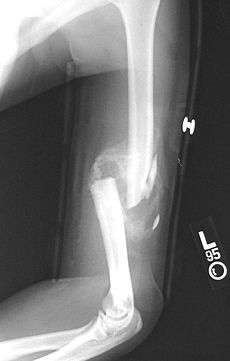

- Non-union: no progression of healing within six months of a fracture occurring. The fracture pieces remain separated and can be caused by infection and/or lack of blood supply (Ischaemia) to the bone.[15] There are two types of non union atrophic and hypertrophic. Hypertrophic involves the formation of excess callus leading to bone ends appearing sclerotic causing a radiological "Elephants Foot" appearance. Atrophic non-union results in re-absorption and rounding of bone ends.[9]

- Mal-union: healing occurs but the healed bone has 'angular deformity, translation, or rotational alignment that requires surgical correction'. This is most common in long bones such as the femur.[16]

- Delayed union: healing times vary depending on the location of a fracture and the age of a patient. Delayed union is characterised by 'persistence of the fracture line and a scarcity or absence of callus formation' on x-ray. Healing is still occurring but at a much slower rate than normal.[15]